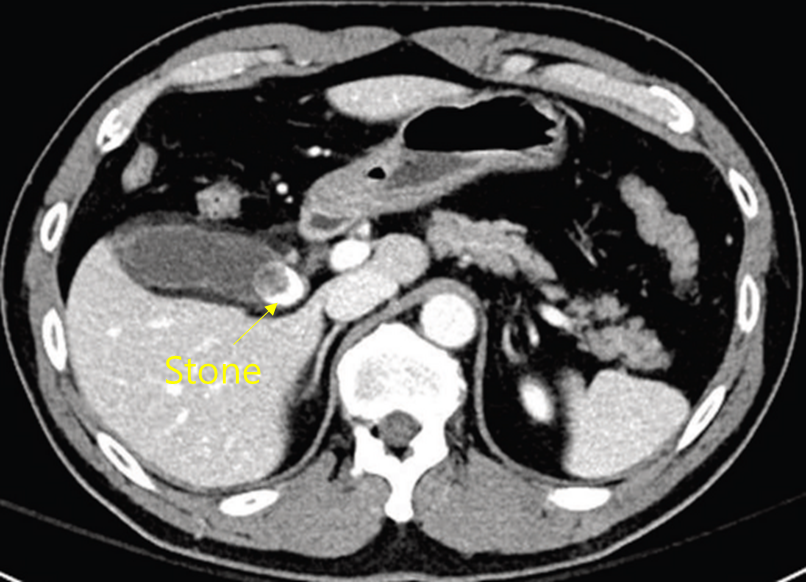

65세 여자가 하루 전부터 열이 나고 배가 아파 응급실에 왔다. 혈압 75/55 mmHg, 맥박 120회/분, 호흡 25회/분, 체온 39.1℃이다. 배 청진에서 장음은 감소하고 오른쪽 윗배에 압통이 있으나 반동압통은 없다. 오른쪽 윗배의 갈비뼈 아래 경계 부위를 가볍게 누른 상태에서 숨을 깊게 들이마시면 갑자기 통증이 유발되어 더 이상 숨을 들이마실 수 없다. 혈액검사 결과는 다음과 같다. 복부 컴퓨터단층촬영 사진이다. 치료는?

Img | CT: Large GB stone, with possible cystic duct obstruction |

• CT상 GB 내부에 GB stone이 확인된다. GB stone으로 인해 acute cholecystitis가 발생하여 septic shock으로 이행되었음을 추정할 수 있다. 위치상 GB가 cystic duct로 이어지는 GB neck 근처에 stone이 있다고 보여지는데, 이 경우 단순 GB stone에서 cholecystitis로 이행될 가능성이 더 높다.